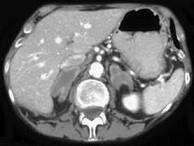

问题 男,65岁,体检时超声发现双侧肾上腺肿块,CT检查如图所示,请结合图像,选择最佳答案()

选项 A.双侧肾上腺转移瘤 B.双侧肾上腺结核 C.双侧嗜铬细胞瘤 D.双侧肾上腺增生 E.双侧肾上腺腺瘤

答案 A